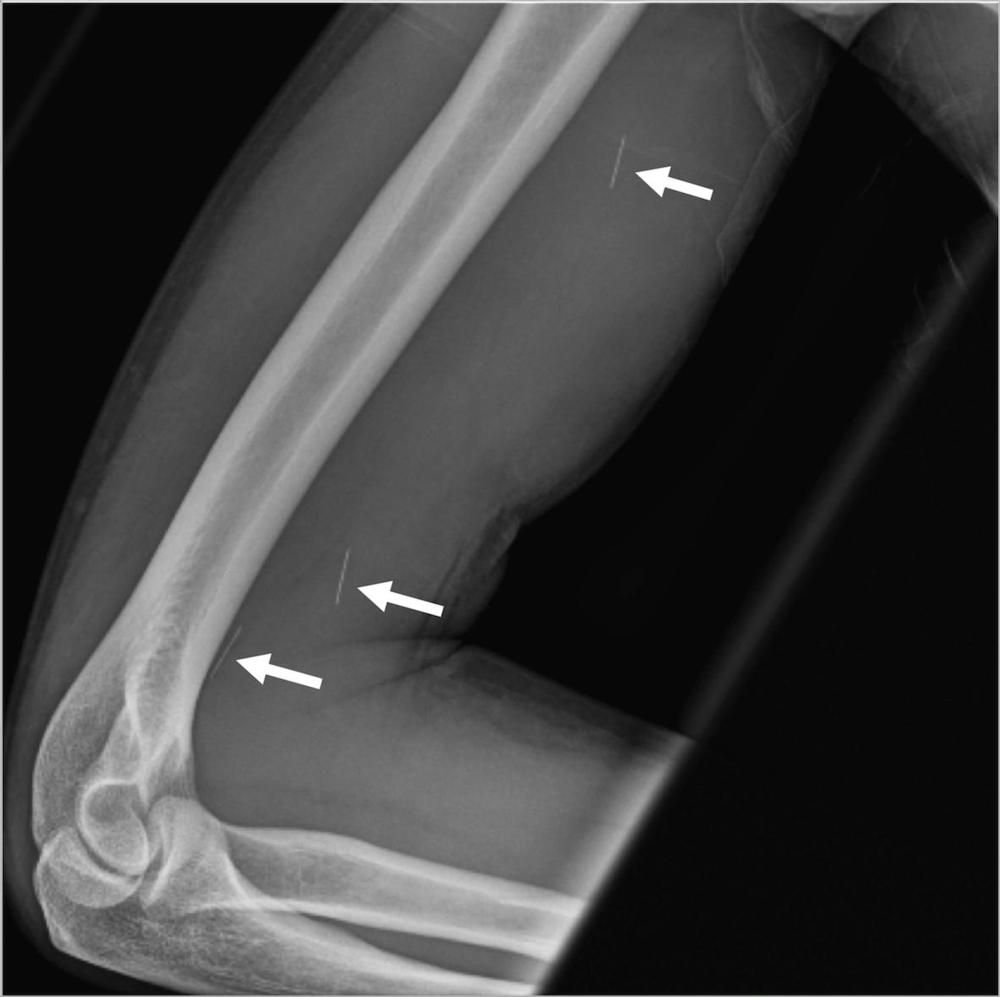

Radiographs can provide anatomic evaluation and appropriate starting point when investigating possible musculoskeletal infection.